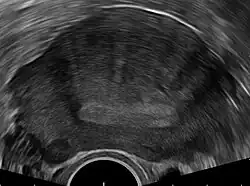

Transvaginal ultrasonography

Transvaginal ultrasound of the uterus, showing the endometrium as a hyperechoic (brighter) area in the middle, with linear striations extending upwards from it

Transvaginal ultrasonography is a cheap and readily available imaging test that is typically used early during the evaluation of gynecologic symptoms.[24] Ultrasound imaging, like MRI, does not use radiation and is safe for examination of the pelvis and female reproductive organs.[25] Overall, it is estimated that transvaginal ultrasonography has a sensitivity of 79% and specificity of 85% for the detection of adenomyosis.[11]

Common transvaginal ultrasound findings are defined by the European MUSA group in 2015 [26] and are defined in 2022 by the MUSA group.[27] The ultrasound characteristics can be divided in direct and indirect features.